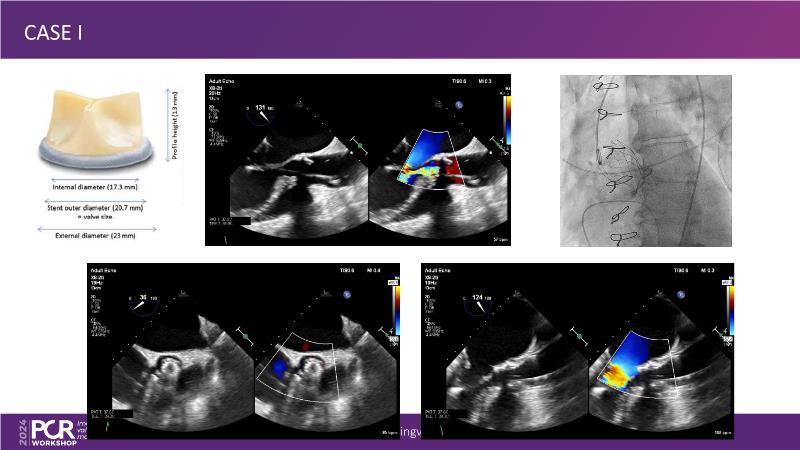

Explore cutting-edge transcatheter valve interventions for mitral and aortic valve disorders, including valve-in-valve procedures and management strategies for paravalvular leakages, and learn about diagnosing and treating mitral annular calcification and transcatheter options in infective endocarditis.

- To manage patients with mixed and multiple valvular heart disease: from risk stratification to therapeutic decision-making

- To get tips and tricks for guidance of transcatheter intervention